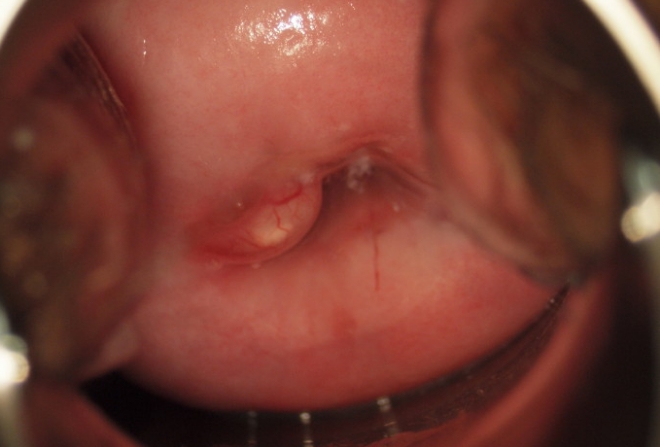

Киста шейки матки — распространенное гинекологическое заболевание, вызывающее беспокойство у женщин. Прижигание кисты — эффективный метод лечения, позволяющий устранить проблему и предотвратить осложнения. В статье рассмотрим процесс процедуры, показания и противопоказания, а также возможные последствия. Эти аспекты помогут женщинам лучше ориентироваться в вопросах здоровья и принимать обоснованные решения о лечении.

Существует несколько способов удаления кисты. Одним из них является прижигание, которое представляет собой процедуру, в ходе которой высокочастотный ток воздействует на пораженные участки тканей. Основная задача этого метода — восстановить проходимость жидкости в железах шейки матки. Прижигание считается одним из самых простых и эффективных способов лечения.

Процесс удаления кист с помощью прижигания включает несколько методов. Каждый пациент может выбрать наиболее подходящий вариант, исходя из своих финансовых возможностей и состояния здоровья. Ниже представлены шесть способов выполнения этой процедуры.